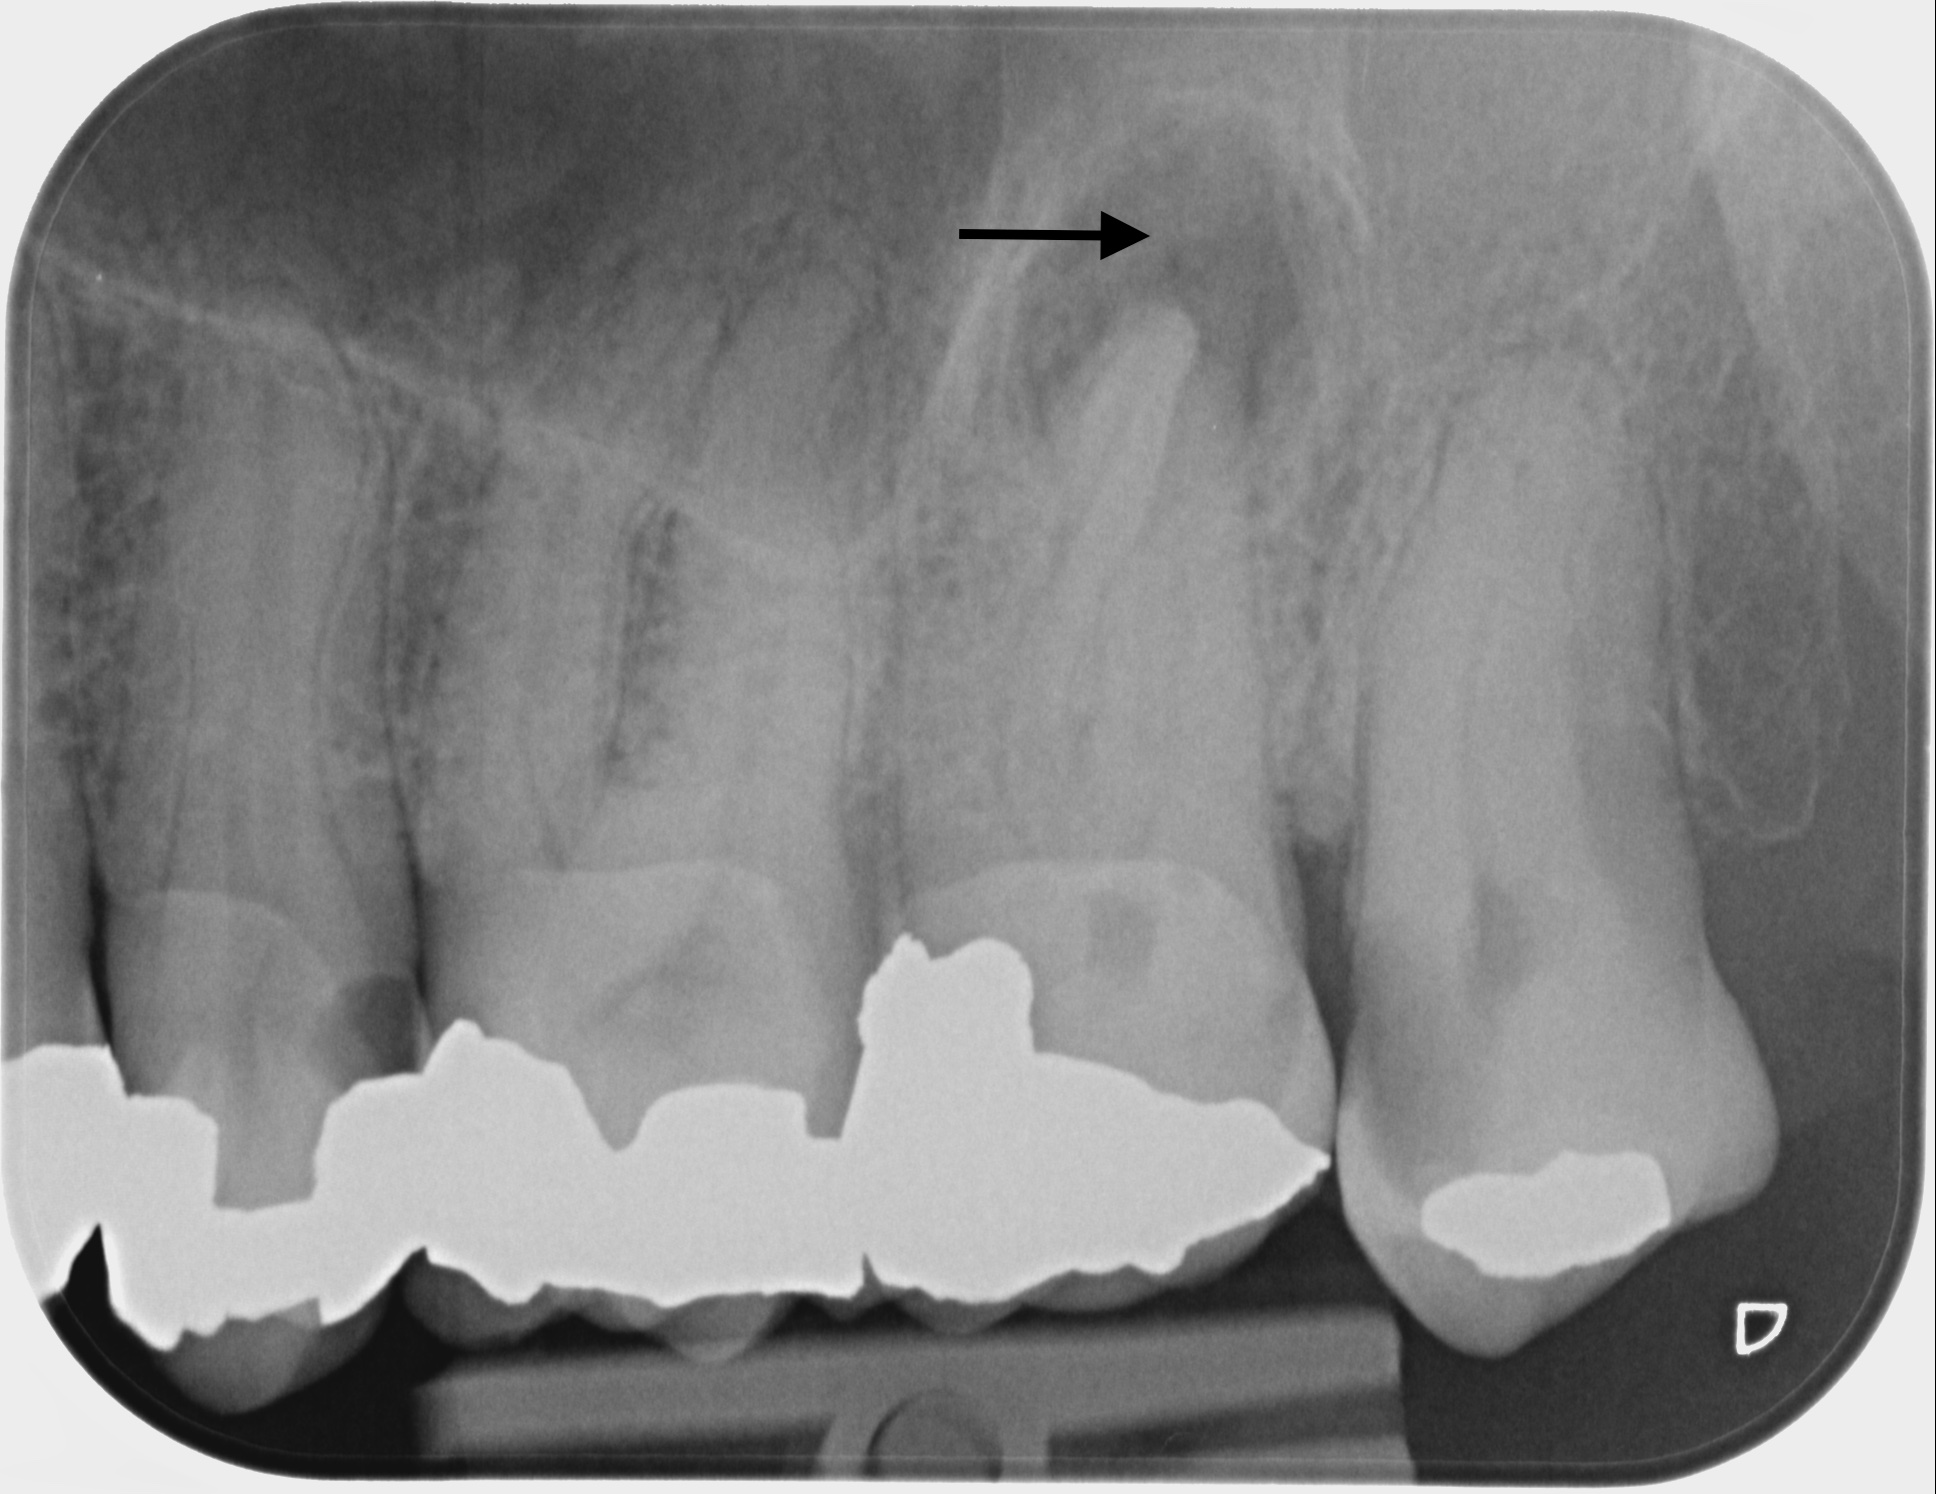

Fallbeispiele

Zum Vergrössern klicken